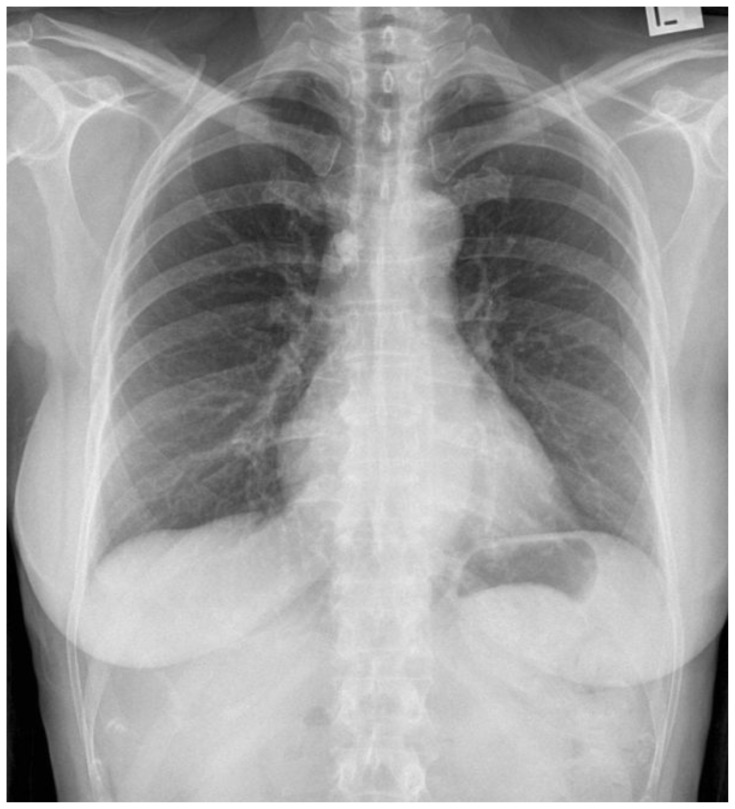

Introduction: Emergency and trauma surgery practitioners routinely perform primary and secondary surveys as a systematic approach to trauma care. While this approach has broad applications, clinicians must also be versed in the nuances of caring for special populations in trauma. One such example is the obstetric patient. The incidence of trauma in pregnancy is increasing and is now the leading cause of non-obstetrical maternal death in the United States.1 Optimal maternal resuscitation depends on an understanding of the significant anatomic and physiologic changes of pregnancy and their influence on airway, breathing, and circulation.2,3,4This case presents a blunt polytrauma with unstable pelvic and lower extremity fractures precipitating hemorrhagic shock and the need for blood product transfusion. Learners must quickly adapt their clinical acumen and consider the influence of an obviously gravid patient on their resuscitation. Implementing and practicing the required skills allows for delivery of high-quality care. This session ensures that learners have a well-rounded understanding of scenarios that could occur in the resuscitation of a pregnant trauma patient.

Educational objectives: At the completion of this simulation participants will be able to 1) perform primary and secondary trauma surveys, 2) assess the neurovascular status of a tibia/fibula fracture, 3) appreciate anatomic and physiologic differences in pregnancy, 4) appropriately order analgesia and imaging, 5) recognize and treat hemorrhagic shock, 6) perform an extended focused assessment with sonography in trauma exam (eFAST) in undifferentiated hemorrhage, 7) identify a displaced pelvic fracture and properly apply a pelvic binder, and 8) obtain and interpret fetal heart rate using ultrasound.

Educational methods: This is a high-fidelity simulation portraying a 24-year-old pregnant female who requires hemodynamic resuscitation, pelvic and extremity fracture stabilization, and assessment of fetal heart rate. After completion of the simulation, learners will participate in a debrief and small group discussion that focuses on didactic knowledge and its application to patient care, crew resource management, and interprofessional communication.